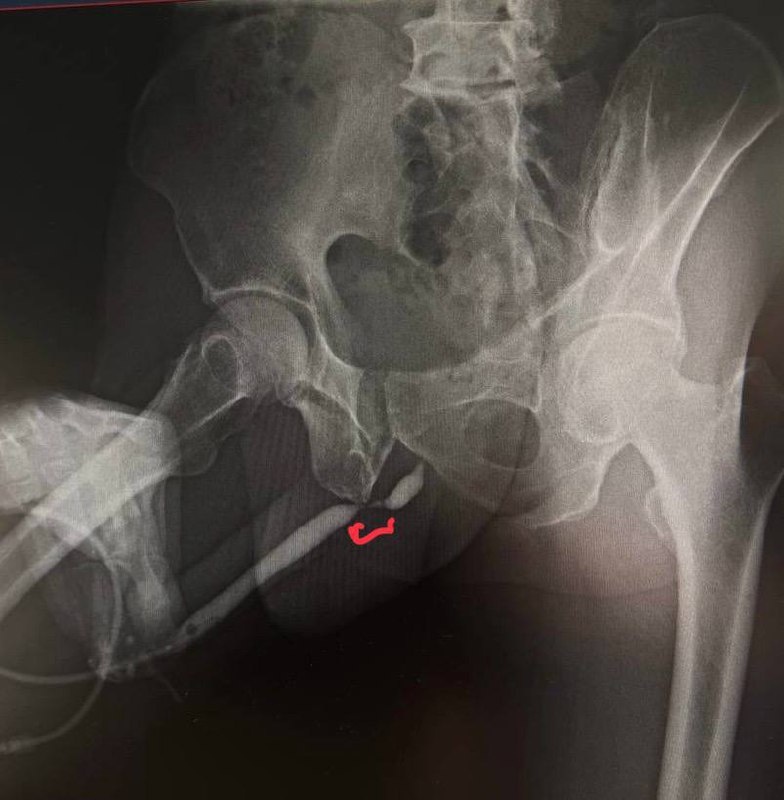

М, 70 Анамнез: 3 года назад перелом полового члена при половом акте с последующим прогрессирующим ухудшением качества мочеиспускания. По материалам обследования: Урофлоуметрия -> Qmax 2.1. УЗИ мочевого пузыря -> 180мл остаточной мочи. Ретроградная уретрография представлена на фото. По урологическому профилю ранее не наблюдался. УЗИ предстательной железы - 42 см3. МИЭФ-5 - 18 баллов. Обрезания не было. Клинический случай на обсуждение от @Mikhaildoctor ☝️ Какая оптимальная хирургическая тактика ? Контакт для связи и публикаций своих материалов - @Aleksei_Mk02

Ретроградная уретрография представлена на фото.